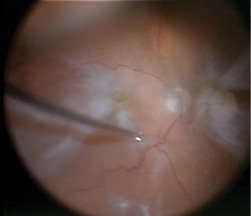

I turned my attention to the posterior pole. Indocyanine green (ICG) was used to stain the ILM (Figure 3), which was gently peeled using the MaxGrip forceps (Figure 4). This was followed by an air-fluid exchange using a soft-tip cannula (MedOne Surgical) taking care to remove all of the subretinal fluid through the draining retinotomy. The retina flattened nicely. Silicone oil (Silikon 1000, Alcon) was infused through the 25-gauge cannula for longer-term tamponade.

Figure 4. Intraoperative photo demonstrating the use of MaxGrip forceps to peel the ILM toward the posterior pole.

The MaxGrip forceps provided the grip needed to gently peel the posterior pole premacular membranes from the surface of the retina. We debated the use of a heavy liquid to stabilize the macula and provide counter traction, but I found that with gentle, constant force directed toward the posterior pole and then toward the stretch hole, I could completely peel the ILM/ERM from the macular surface. Repeated regrasping at the base of the membrane minimized movement of the retina and allowed for maximum control of the removal of the posterior membrane in terms of force and direction (Figure 6).

Figure 5. Intraoperative image of the ERM being regrasped at the base and peeled toward the stretch hole in the periphery.